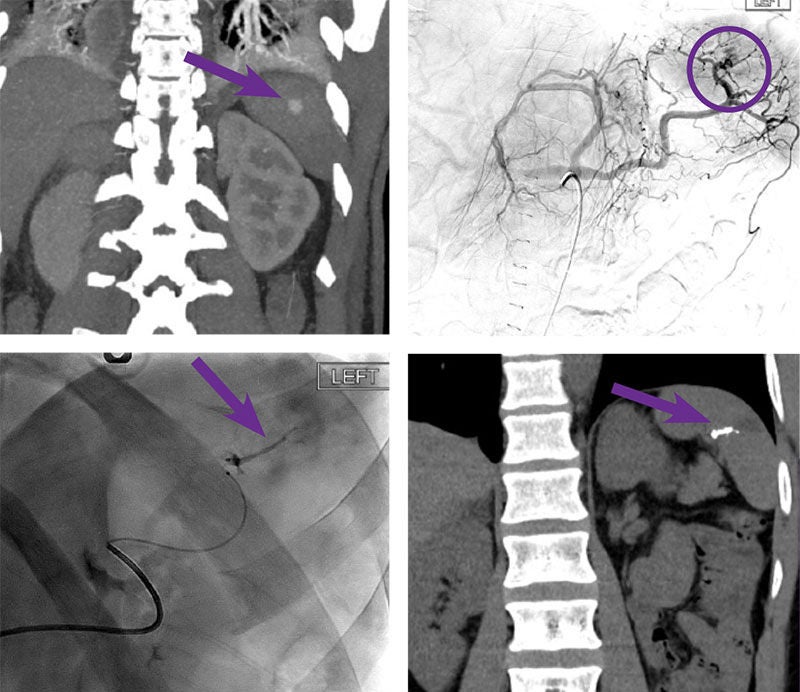

Splenic pseudoaneurysm embolization

Courtesy of Dr. Mikin Patel I University of Chicago

45-year-old male, pedestrian vs auto with multiple injuries. Emergent left diaphragmatic rupture repair, reduction of stomach, and left tube thoracoscopy. CT demonstrated a moderate sized hemoperitoneum.

Arterial access was gained via the right common femoral artery. RC1 catheter was then used to select the celiac artery and an angiogram was performed. There is a pseudoaneurysm arising from a segmental branch of the superior aspect of the spleen. Using a Glidewire™ Hydrophilic Coated Guidewire, the RC1 catheter was advanced into the splenic artery near the hilum and repeat angiogram was performed. No evidence of arterial extravasation. A 2.8 F Progreat™ Microcatheter, as well as a microwire were then navigated into the abnormal superior segmental splenic artery branch with small amount of contrast injected confirming appropriate position. Next, the superior segmental splenic artery branch was embolized using 0.2 cc of Obsidio Embolic.

Outcome

Patient stabilized post procedure however required surgical repair of diaphragmatic rupture.